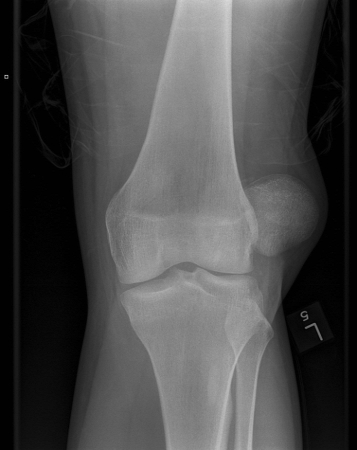

Joint dislocation

Left knee radiograph demonstrating lateral patella dislocation

Yerimah G, et al. BMJ Case Rep. 2013 May 2:2013:bcr2013009832; used with permission